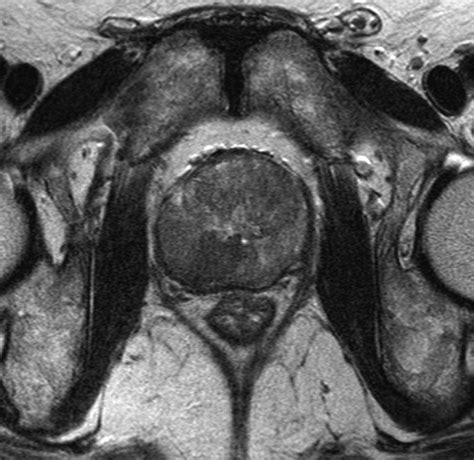

• Multiparametric MRI (mpMRI): This technique combines multiple MRI sequences, including T2-weighted imaging, diffusion-weighted imaging (DWI), and dynamic contrast-enhanced (DCE) imaging, to provide a comprehensive evaluation of the prostate.

• Prostate Imaging Reporting and Data System (PI-RADS): This standardized reporting system helps radiologists interpret MRI findings and classify the likelihood of clinically significant prostate cancer.